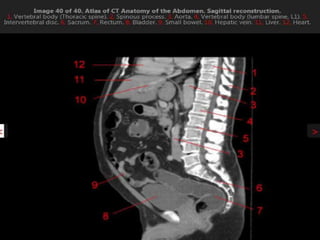

CT cross sectional anatomy.